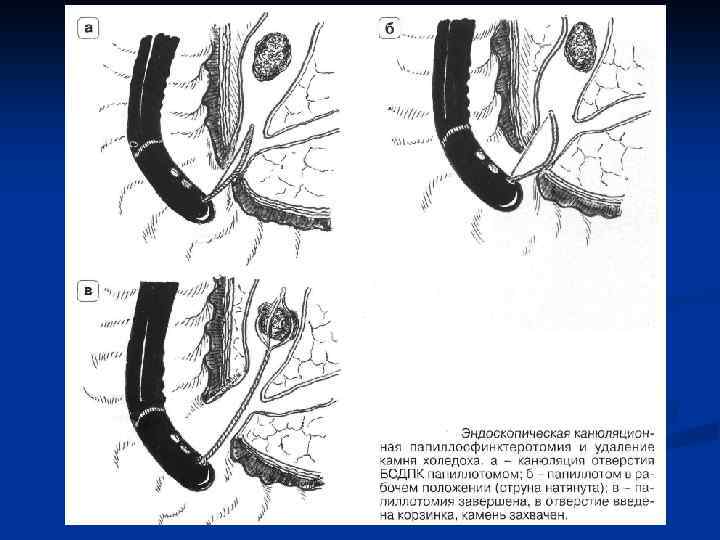

Лечение холангиолитиаза Холангиолитиаз устраняется с помощью эндоскопических методов после выполнения РХПГ. Выполняется эндоскопическая папиллосфинктеротомия в сочетании с удалением камней из холедоха петлей Дормиа, катетером Фогарти n Лапаротомия с холедохотомией – альтернативный метод лечения. n

Лечение холангиолитиаза Холангиолитиаз устраняется с помощью эндоскопических методов после выполнения РХПГ. Выполняется эндоскопическая папиллосфинктеротомия в сочетании с удалением камней из холедоха петлей Дормиа, катетером Фогарти n Лапаротомия с холедохотомией – альтернативный метод лечения. n